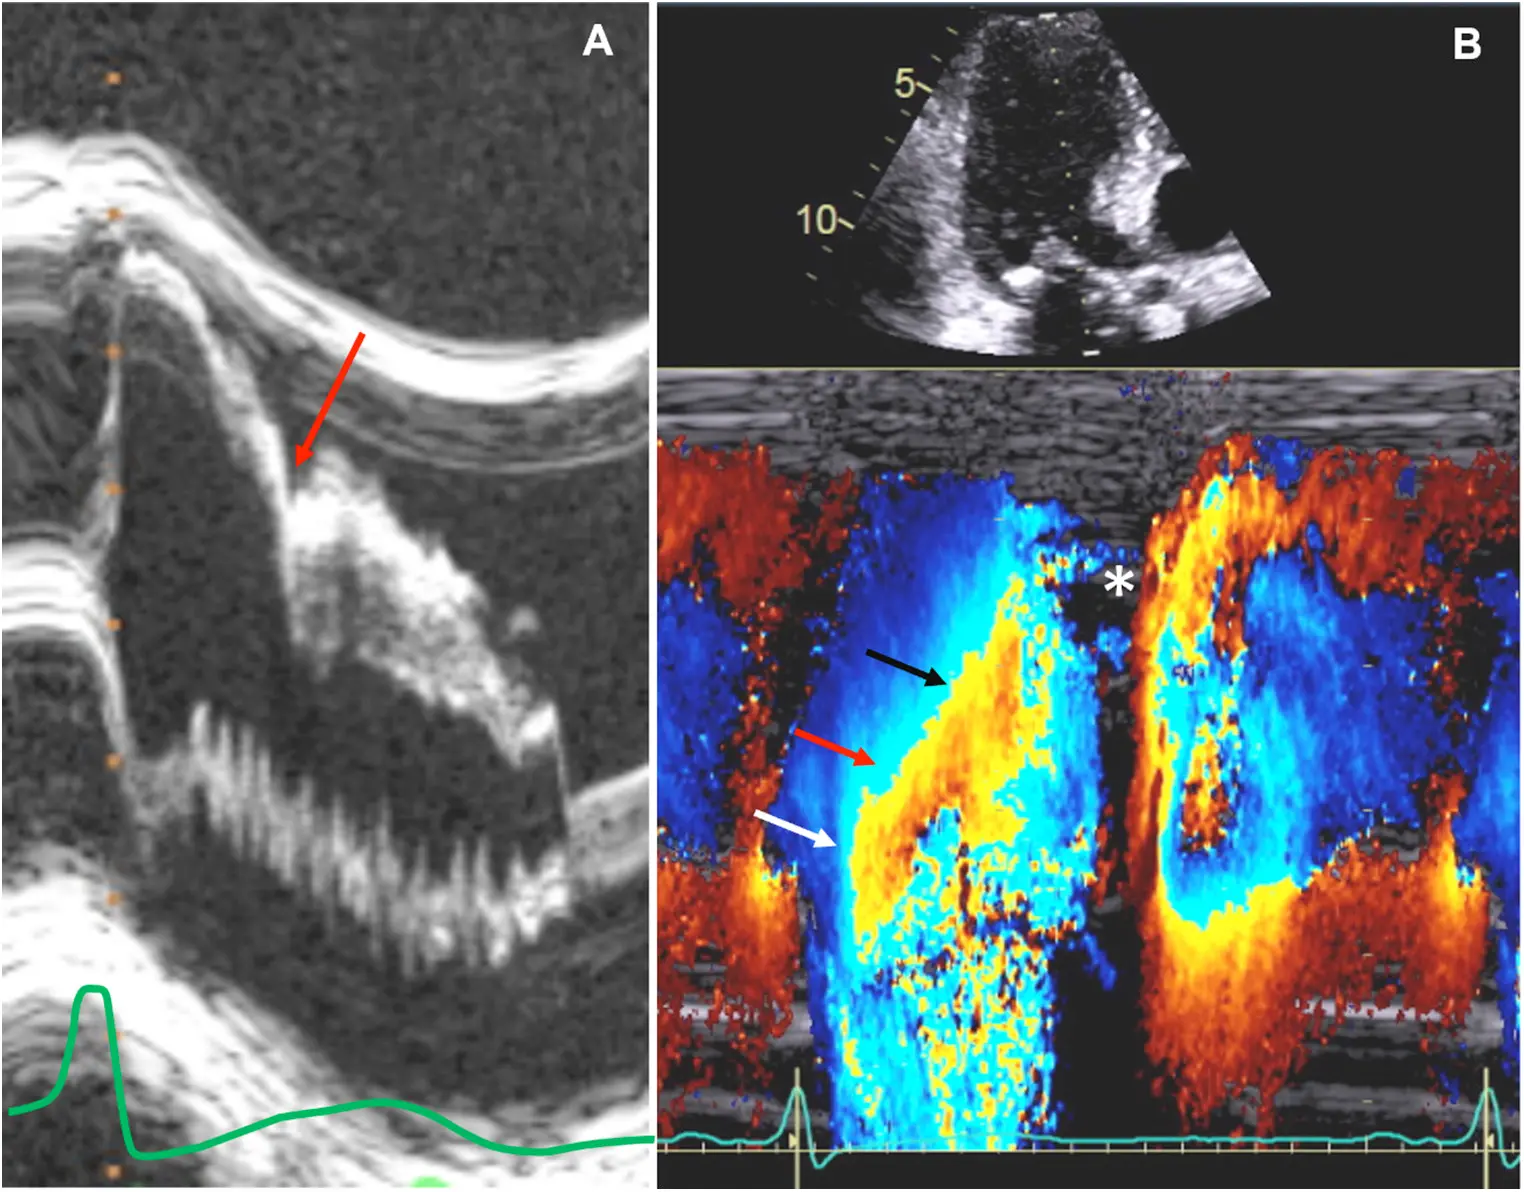

Cardiac MRI in HCM

Offers superior image quality compared to echocardiography and can be crucial in confirming the diagnosis, especially in cases of challenging echocardiographic windows. CMR can also detect myocardial fibrosis, a prognostic indicator in HCM.